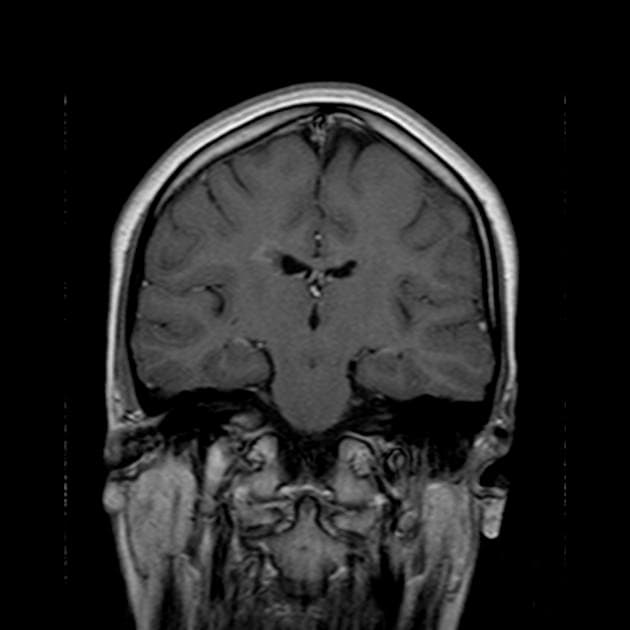

Chụp cộng hưởng từ (MRI) cho thấy các đặc điểm điển hình của bệnh xơ cứng rải rác. Ngoài ra, một số tổn thương có tín hiệu tăng trên hình ảnh T1 (T1 hyperintense).

Các phát hiện chính:

- Các tổn thương rải rác, dạng vệt hoặc hình tròn, tăng tín hiệu trên hình ảnh khuếch tán (diffusion-weighted imaging), khu trú chủ yếu ở vùng chất trắng quanh thất (periventricular white matter), chất trắng ở bán nguyệt (juxtacortical white matter), thân gai thị – giao thoa thị giác (optic radiation – optic chiasm), và thân não (brainstem) – phù hợp với đặc điểm của xơ cứng rải rác (multiple sclerosis).

- Thể chai (corpus callosum) có tổn thương dạng dải ngang (Dawson's fingers) – đặc trưng của xơ cứng rải rác (multiple sclerosis).

- Các não thất và khe não bình thường về kích thước, không thấy giãn não thất (hydrocephalus) hay xóa (rãnh não/bể não) (effacement).